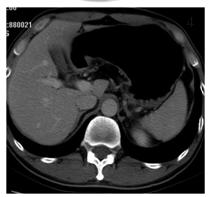

主要强调增强时相和多平面重组技术。动脉晚期(40 s)增强有助于肿瘤胃壁的充分强化(如图1),多期增强则有助于显示分层强化特征,通过上述技术联合加上显示率微调,可有效提高T分期的准确率。